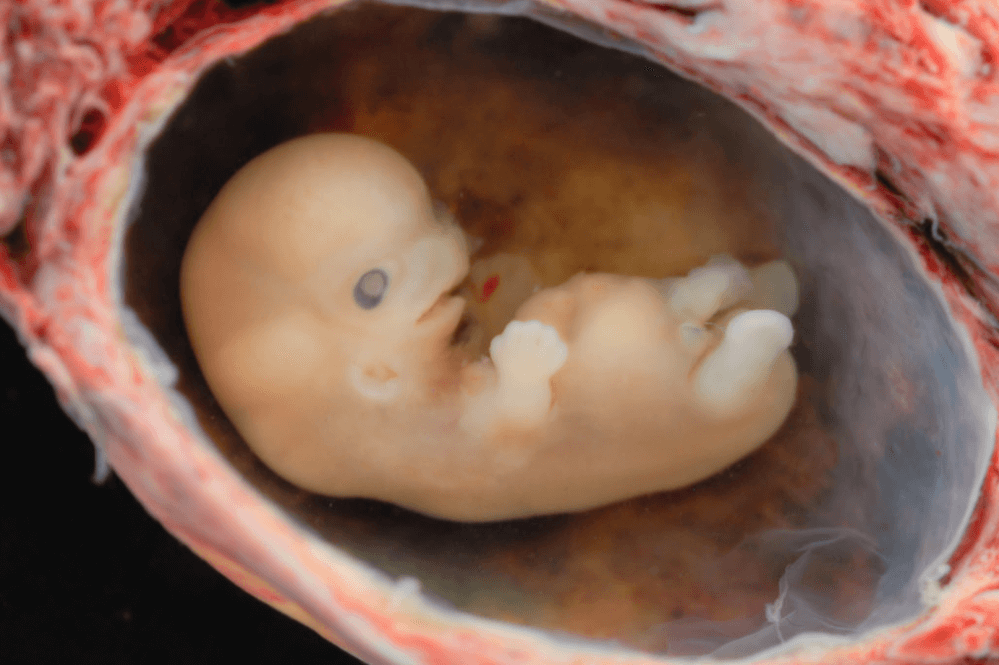

«Αυτός ο νόμος αναγνωρίζει το επιστημονικό δεδομένο που το κίνημα υπέρ των αμβλώσεων προσπαθεί να εναγωνίως να αντιπαρέλθει: Αυτό που βρίσκεται στη μήτρα είναι μια ξεχωριστή ανθρώπινη ζωή και όχι μια μάζα κυττάρων…», είπε η Rose, «… και η μικρή καρδούλα του εμβρύου ήδη χτυπά, μόλις τρεις εβδομάδες μετά τη γονιμοποίηση. Είναι καιρός για την κοινωνία και τους νόμους μας να αναγνωρίσουν ότι σε μία εγκυμοσύνη υπάρχουν δύο άνθρωποι που και οι δύο δικαιούνται προστασίας».

Μια μελέτη του Πανεπιστημίου της Οξφόρδης έδειξε ότι η καρδιά ενός εμβρύου, που δεν έχει γεννηθεί, μπορεί να αρχίσει πραγματικά να χτυπά περίπου 16 μέρες από την έναρξη της κυήσεως, αν και αρχικά η επικρατούσα αντίληψη τοποθετούσε αυτό το γεγονός στην τρίτη εβδομάδα. Η Αϊόβα είναι αυτή τη στιγμή η πιο ασφαλής Πολιτεία για τα αγέννητα παιδιά σε ολόκληρη τη χώρα.